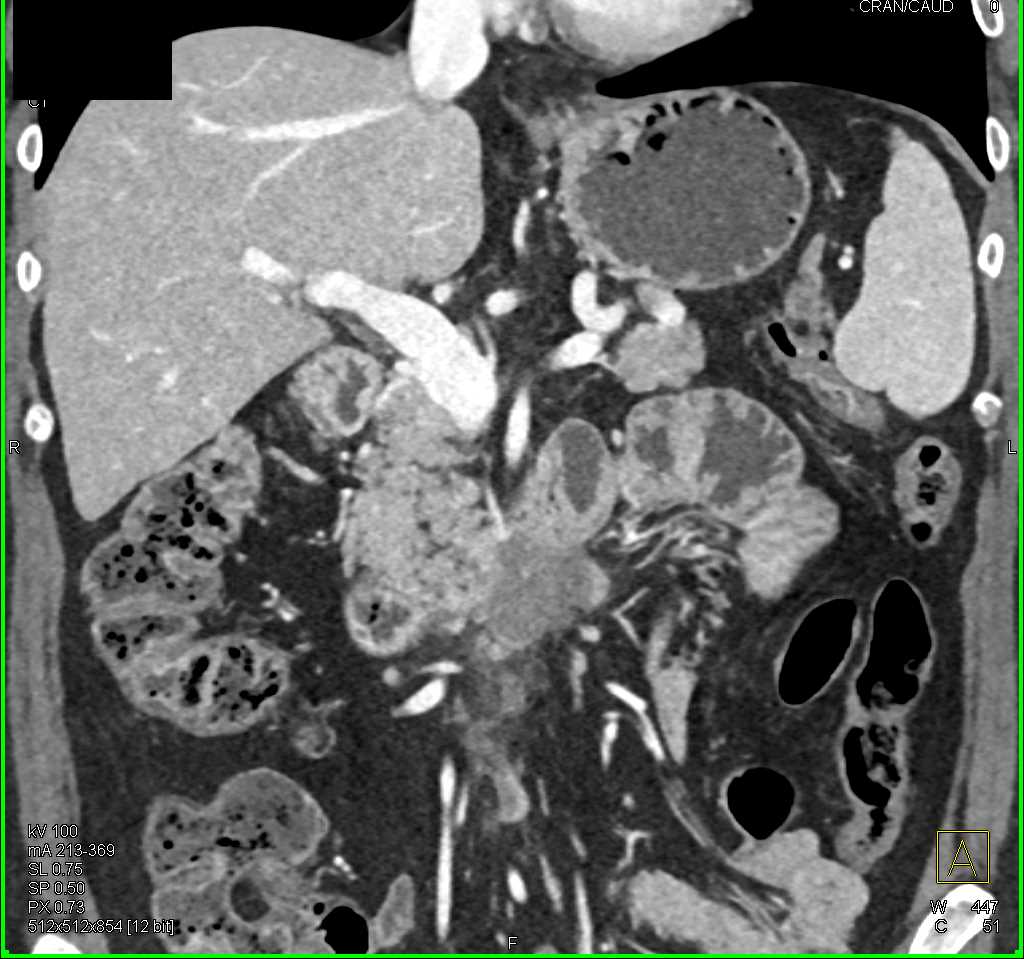

Duodenal Carcinoma with Obstruction